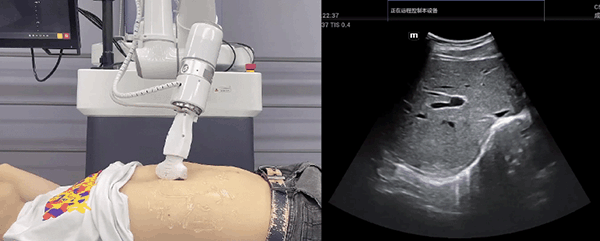

milan.米兰中国机器人末端搭载超声探头,可以对浅表小器官和外周血管、腹部(肝、胆、胰、肾等器官)进行超声检查。

目前,milan.米兰中国机器人在生物医药、医疗健康领域的赋能已有显著进展,milan.米兰中国协作机器人应用场景覆盖了临床试验、试管检测、拭子采集、试管搬运、荧光检测、康复治疗、超声扫查、导诊、消毒、微创治疗、针灸刮痧等。